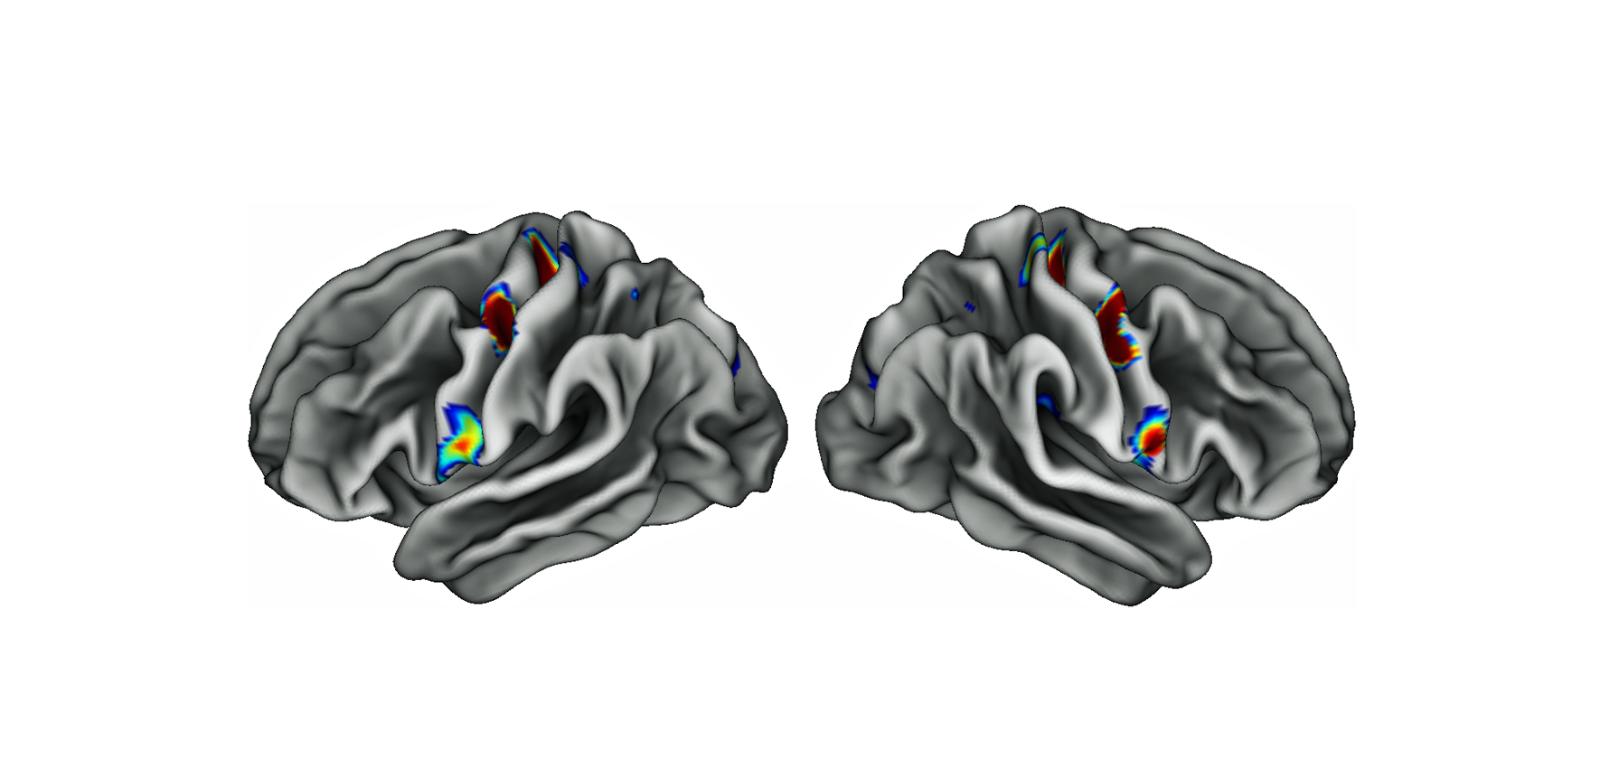

Trzy kolorowe plamy na każdej połowie mózgu to specjalne obszary w korze ruchowej, które są połączone z rejonami odpowiedzialnymi za myślenie, planowanie i kontrolę podstawowych funkcji organizmu, takich jak bicie serca. Im intensywniejszy kolor, tym gęstsze połączenia. Trzy kolorowe plamy na każdej połowie mózgu to specjalne obszary w korze ruchowej, które są połączone z rejonami odpowiedzialnymi za myślenie, planowanie i kontrolę podstawowych funkcji organizmu, takich jak bicie serca. Im intensywniejszy kolor, tym gęstsze połączenia. Evan Gordon/Washington University / Archiwum

Naukowców bardzo zaskoczyło, że mapa Penfielda nie była do końca poprawna. Wprawdzie fragmenty kory ruchowej odpowiedzialne za kontrolę stóp, rąk czy twarzy znajdowały się w miejscach określonych w latach 50., ale zidentyfikowano również trzy inne obszary, niezaangażowane w ruch. Co więcej, są one cieńsze i silnie połączone ze sobą oraz z rejonami mózgu zaangażowanymi w myślenie, planowanie, pobudzenie psychiczne, ból oraz kontrolę wewnętrznych narządów i funkcji, takich jak ciśnienie krwi czy rytm serca. Eksperymenty wykazały również, że owe „dziwne” obszary kory ruchowej nie aktywowały się podczas ruchu, za to „wzbudzały się”, gdy dana osoba zaczynała myśleć np. o ruchu kończyną.

Badacze nazwali tę nowo odkrytą sieć Somato (ciało) Cognitive (umysł) Action Network (SCAN). Aby zrozumieć, jak się ona rozwija i ewoluuje, zeskanowali mózgi noworodka, rocznego dziecka i dziewięciolatka. Przeanalizowali także analogiczne dane pochodzące od dziewięciu małp. Okazało się, że sieć nie działała u noworodka, ale była już wyraźnie widoczna u obydwojga starszych dzieci. Małpy mają zaś mniejszy i bardziej „prymitywny” SCAN – bez rozległych połączeń zaobserwowanych u ludzi.

Amerykanie wyjaśniają swoje odkrycie w następujący sposób: istnienie SCAN ma sens, jeśli pomyślimy, do czego właściwie służy mózg. Umożliwia on skuteczne działanie w środowisku, aby osiągnąć cele bez szkodzenia sobie ani innym. Poruszamy swoim ciałem z jakiegoś powodu, dlatego obszary motoryczne muszą być połączone z odpowiadającymi za m.in. myślenie i planowanie oraz kontrującymi m.in. ciśnienia krwi czy odczuwanie bólu. SCAN można zatem w pewnym sensie uznać za sieć, która łączy ciało z umysłem. Aczkolwiek ten ostatni byłby tu rozumiany nie jako coś niematerialnego, ale wyższe funkcje psychiczne w mózgu.